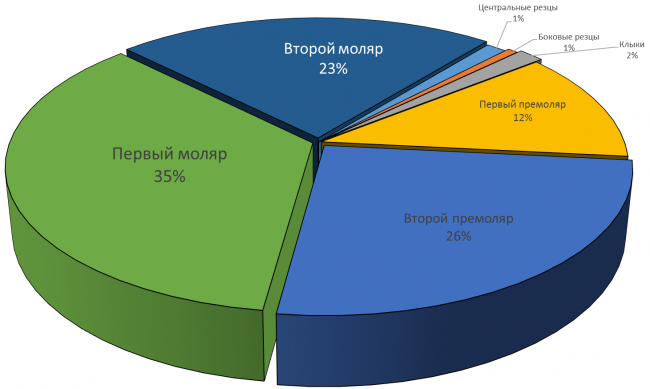

Так ли это на самом деле? Я тут проанализировал собственные данные за 2013 год (статистику 2014 года еще не считал). Главный вопрос, который я перед собой поставил, звучит как:

В КАКИЕ ОБЛАСТИ ПРИХОДИТСЯ СТАВИТЬ ИМПЛАНТЫ ЧАЩЕ ВСЕГО?

Вот 630 одиночных имплантов (не являющиeся опорами мостовидных или иных конструкций), установленных за 2013 год.

Что показывают эти диаграммы?

А показывают они то, что чаще всего приходится имплантировать (в т. ч. немедленно) зубы в боковом участке челюсти: от пятерки до семерки это суммарно около 83% на верхней и 84% на нижней челюсти. Доля зубов фронтальной группы (резцы, клыки, первые премоляры) не очень велика — почти 27% на верхней и менее 16% на нижней челюсти.

Это легко объяснить — утрата или повреждение зуба в зоне улыбки влечет за собой эстетический дефект, поэтому люди изо всех сил стараются их сохранить. К тому же, нагрузка на эти зубы меньше, их легче чистить, а любые, даже самые минимальные их повреждения легко заметить.

Чего не скажешь о больших коренных зубах. Некоторые пациенты на предложение имплантировать давно отсутствующую шестерку задают вопрос: «А зачем? Его же не видно!», не понимая важной функциональной роли боковых зубов.